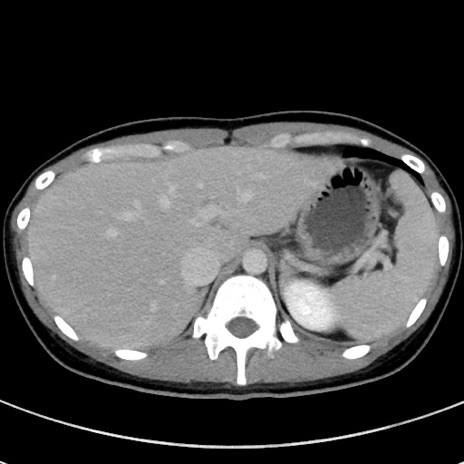

症例17(横断像)

【症例】20歳代女性

【主訴】嘔吐、下腹部痛

【現病歴】昨日夕食後に嘔吐し下腹部痛が出現。本日になっても嘔吐持続し改善しないため来院。

【身体所見】意識清明、BT 37.2℃、BP 108/67mmHg、腹部:平坦、やや硬、下腹部正中から右にかけて圧痛あり、反跳痛軽度あり、tapping pain(+)。

【データ】WBC 13600、CRP 14.94